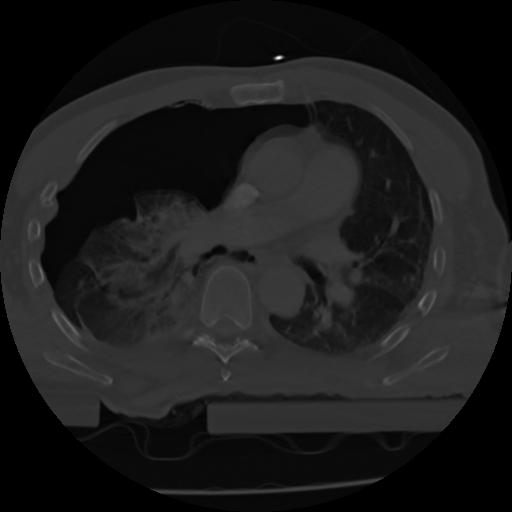

21 ANGIO,CE,Axial,3.0,ANGIO,,